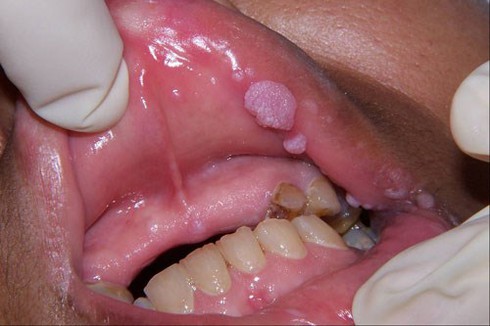

Sùi mào gà |

Sùi mào gà là một trong số 8 căn bệnh lây nhiễm qua đường tình dục, mức độ nguy hại của nó đối với sức khỏe con người không thể coi nhẹ. Sùi mào gà là bệnh lây truyền qua đường tình dục do nhiễm HPV, biểu hiện bằng các sẩn sùi mềm ở sinh dục ngoài có khi ở hậu môn hoặc vùng da khác như ở miệng. Tác nhân gây bệnh là HPV (human papiloma virus), thuộc loại papova virus có DNA. Chủ yếu lây truyền qua đường tình dục, còn có thể lây truyền qua tiếp xúc. Trẻ sơ sinh có thể bị lây bệnh từ người mẹ mắc bệnh trong lúc sinh đẻ.